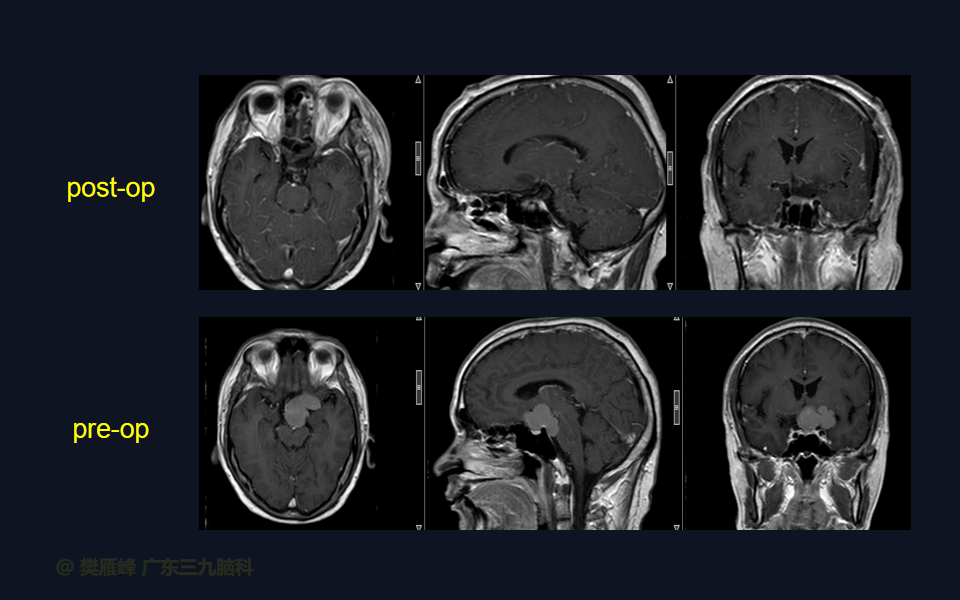

在这个二维手术视频中,展示了一种经翼点入路颅咽管瘤。患者是一名50岁的男性,有1月的左眼视物模糊、无多饮多尿病史,神经影像学显示鞍上区-桥前池示一团块状短T1长T2,Flair序列高信号,分叶状,边缘轻度线样强化,大小约47.5×33×33mm,邻近左侧颈内动脉-大脑前、中动脉局部受包绕的鞍上的颅咽管瘤。经术前讨论选择经扩大翼点入路颅咽管瘤切除,以实现肿瘤全切除,保护周围神经血管。术后术后尿量增多,10天后好转;视力、视野同术前改变;神经影像学显示肿瘤全部切除。我们展示了安全的神经血管保护和肿瘤切除术的细微差别和技术要点,以及手术技术。